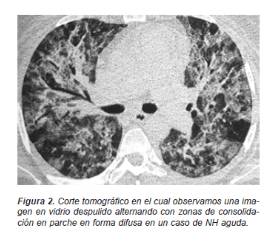

En las formas agudas de la NH se presenta un aumento de la densidad parenquimatosa con una atenuación en vidrio despulido en parches o difusa del espacio aéreo (Figura 2).

En la fase subaguda predominan las imágenes redondas, pequeñas, mal definidas de distribución difusa, pero con una preferencia broncocéntrica que usualmente se verán sumadas a los cambios agudos (Figura 3).

En cambio los casos crónicos presentan un patrón nodular sumado a opacidades reticulares finas y gruesas (patrón reticulonodular) de predominio central con engrosamiento del intersticio broncovascular, que en forma paulatina progresan a una imagen de conglomerados fibróticos o áreas quísticas o en «panal de abeja» (Figura 4).